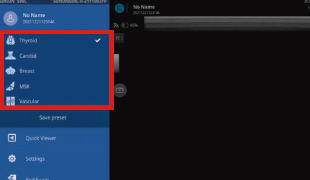

SONONは、「いつでも、どこでも、簡単に」を実現させるために、とことんユーザーインターフェース(UI)にこだわりました。よく使う機能を常に表示し、極力ボタン操作を少なくできるよう設計。直感的な操作で「見る」「撮る」「測る」「保存する」「呼び出す」ことができ、診療科に適した各種設定をプリセットしているため、エコー初心者でも簡単に使用できる操作性を実現しました。

ストレスフリーな操作性

主な検査モードはプリセットされており、目的にあわせた検査モードを選択するだけ。ストレスなく簡単に検査することができます。(500L…7モード、300C…6モード)